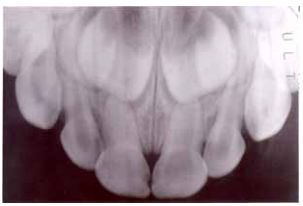

54 有位 3 歲半男孩兩天前在遊樂場跌倒,口腔檢查上唇擦傷,上顎門牙動搖性略增,其 X 光片如圖, 則應如何處置? (A)立即拔除右上正中門牙 (B)立即對右上正中門牙施行根管治療 (C)固定前牙 6-8 周並追蹤觀察 (D)建議追蹤觀察即可